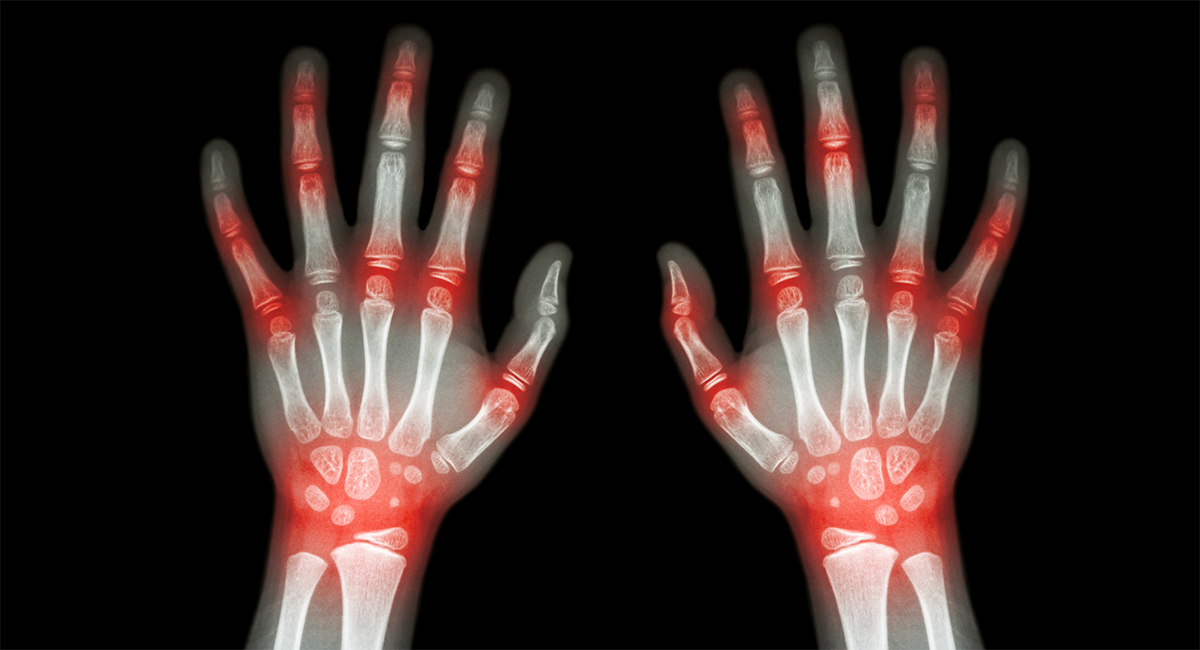

Суставы кистей находятся под тонким слоем мягких тканей, поэтому любые патологические процессы в них быстро приводят к заметным деформациям и изменяют рельеф поверхности. Безусловно, это не делает руки красивее, но в то же время и не позволяет откладывать решение проблемы на потом. А это очень важно. Потому что внешние локальные изменения нередко свидетельствуют о серьезных системных заболеваниях.

Шишки на руках и деформация пальцев — каковы причины?

Любые изменения контуров кисти свидетельствуют о структурных изменениях тканей. Поэтому ошибочно относиться к ним только как к косметическому дефекту. И не стоит сразу пытаться устранить их с помощью рецептов, почерпнутых у подруг и знакомых, страдавших «такими же шишками» и чудесным образом излечившихся народными средствами.

Наиболее распространенные заболевания, приводящие к деформации кистей, это:

— артрит — инфекционный (при попадании инфекции в полость сустава) или аутоиммунный, например, ревматоидный. В суставе развивается воспалительный процесс, сопровождающийся деструкцией и отеком. Сустав внешне увеличивается в размерах, кожа над ним краснеет и становится горячей. Хроническое течение воспаления приводит не к столь бурным, но непрерывно продолжающимся разрушениям, которые не могут не сказаться на форме сустава;